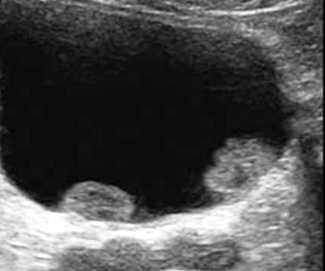

УЗ-признаки рака МП

Подготовка к УЗИ при подозрении на рак аналогична указанной выше. С помощью ультразвукового обследования устанавливают локализацию опухоли, ее структуру, размеры, особенности кровоснабжения. Одновременно исследуют вовлечение в опухолевый процесс мочеточников, простаты у мужчин, яичников и маточных труб у женщин, определяют наличие метастазов в регионарных лимфоузлах. Легче диагностируются экзофитно растущие опухоли (внутрь полости) мочевого пузыря размером более 5 мм. При инфильтративном раке, прорастающем в толщу стенки (эндофитная опухоль), ультразвуковая диагностика менее информативна.

Ультразвуковыми признаками рака, расположенного в мочевом пузыре, являются:

- изо- или гиперэхогенные образования на стенках органа с неоднородной структурой,

- гиперэхогенные мелкие образования на дне пузыря (скопления некротических масс и сгустков крови при распадающейся опухоли);

- неровные стенки органа, неравномерное изменение их толщины и однородности;

- деформации пузыря.